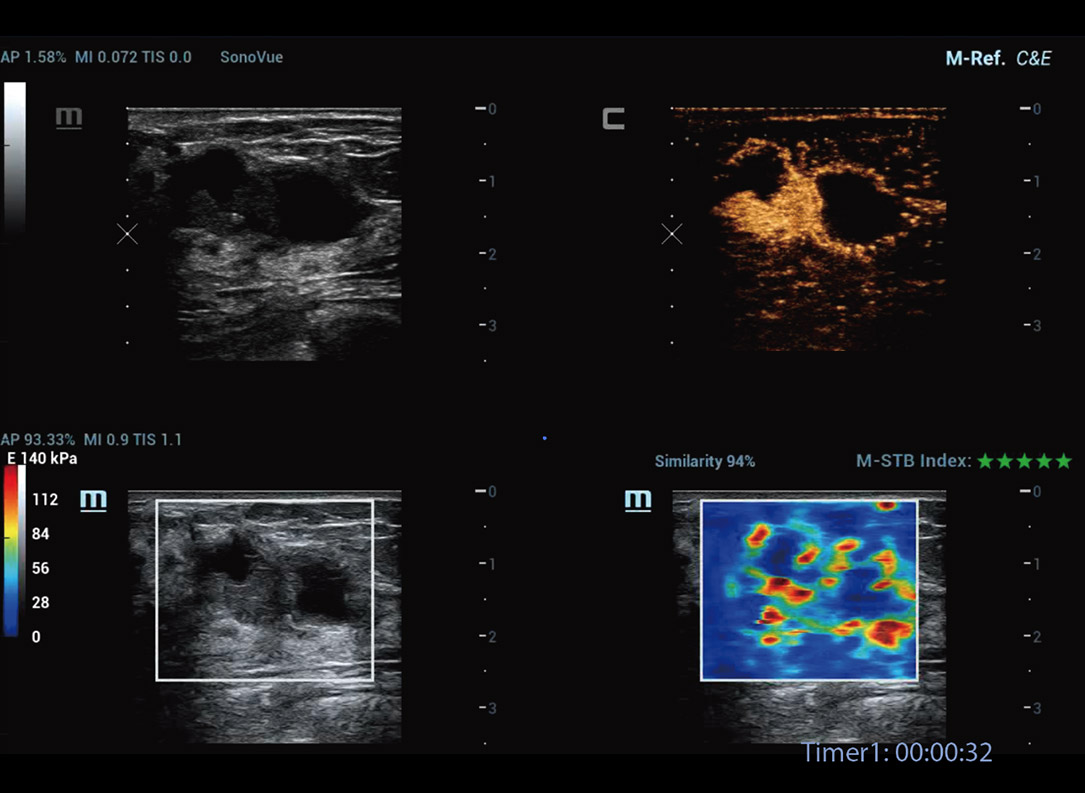

Strumenti di analisi multiparametrica M-Reference

M-Ref. C&E

M-Ref. C&E tumore maligno al seno

M-Ref. C&E supporta la visualizzazione del contrasto e della STE in un unico piano per una valutazione comparativa della perfusione e dell'elasticitĂ .

M-Ref. E Compare

M-Ref. E Compare tumore maligno al seno

M-Ref. E Compare supporta la visualizzazione dell'elastografia strain in tempo reale e della STE in un unico piano per la valutazione della rigiditĂ dei tessuti.

Nuova analisi quantitativa CEUS

Nuova QA CEUS tumore maligno al seno

La curva tempo-intensitĂ offre un'analisi quantitativa dell'imaging CEUS. La Nuova QA CEUS fornisce strumenti di analisi quantitativa all'avanguardia per la valutazione dei tumori e la ricerca clinica.